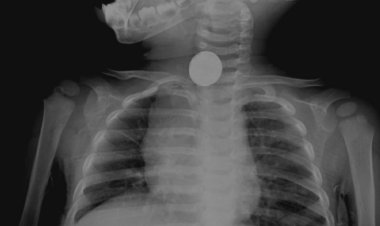

Çin'deki salgının ardından Hollanda'da çocukluk çağı zatürresinde...

Sağlık kuruluşları, Hollanda ve Çin'de çocukluk çağı zatürre vakalarının arttığını bildirdi. Solunum yolu enfeksiyonlarındaki gizemli...

Güneybatı Ohio'da çocukluk çağı zatürre salgını bildirildi:...

Ohio'nun güneybatısındaki Warren County'de pediatrik bir pnömoni salgını rapor edildi. Warren County Sağlık Bölgesi, ağustos ayından...